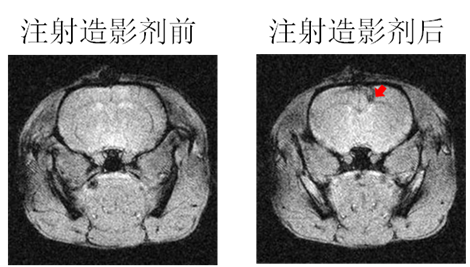

磁性纳米材料作为磁共振(MRI)造影剂的应用